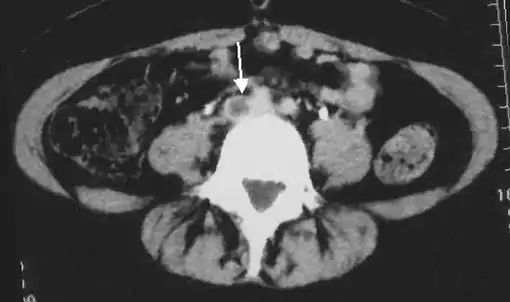

DVT in the legs is proximal when above the knee and distal (or calf) when below the knee.[47] DVT below the popliteal vein, a proximal vein behind the knee, is classified as distal[48] and has limited clinical significance compared to proximal DVT.[49] Calf DVT makes up about half of DVTs.[50] Iliofemoral DVT has been described as involving either the iliac or common femoral vein;[51] elsewhere, it has been defined as involving at a minimum the common iliac vein, which is near the top of the pelvis.[19]

An abdominal CT scan demonstrating an iliofemoral DVT, with the clot in the right common iliac vein of the pelvis